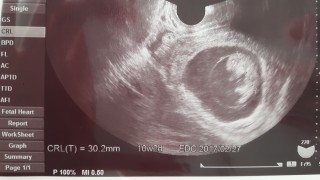

8wは16mm、9w5dの今日は30.2mmでした(^o^) 大きさでいうと10w2d並みたいです。 つわりは辛いですが順調で何よりです。